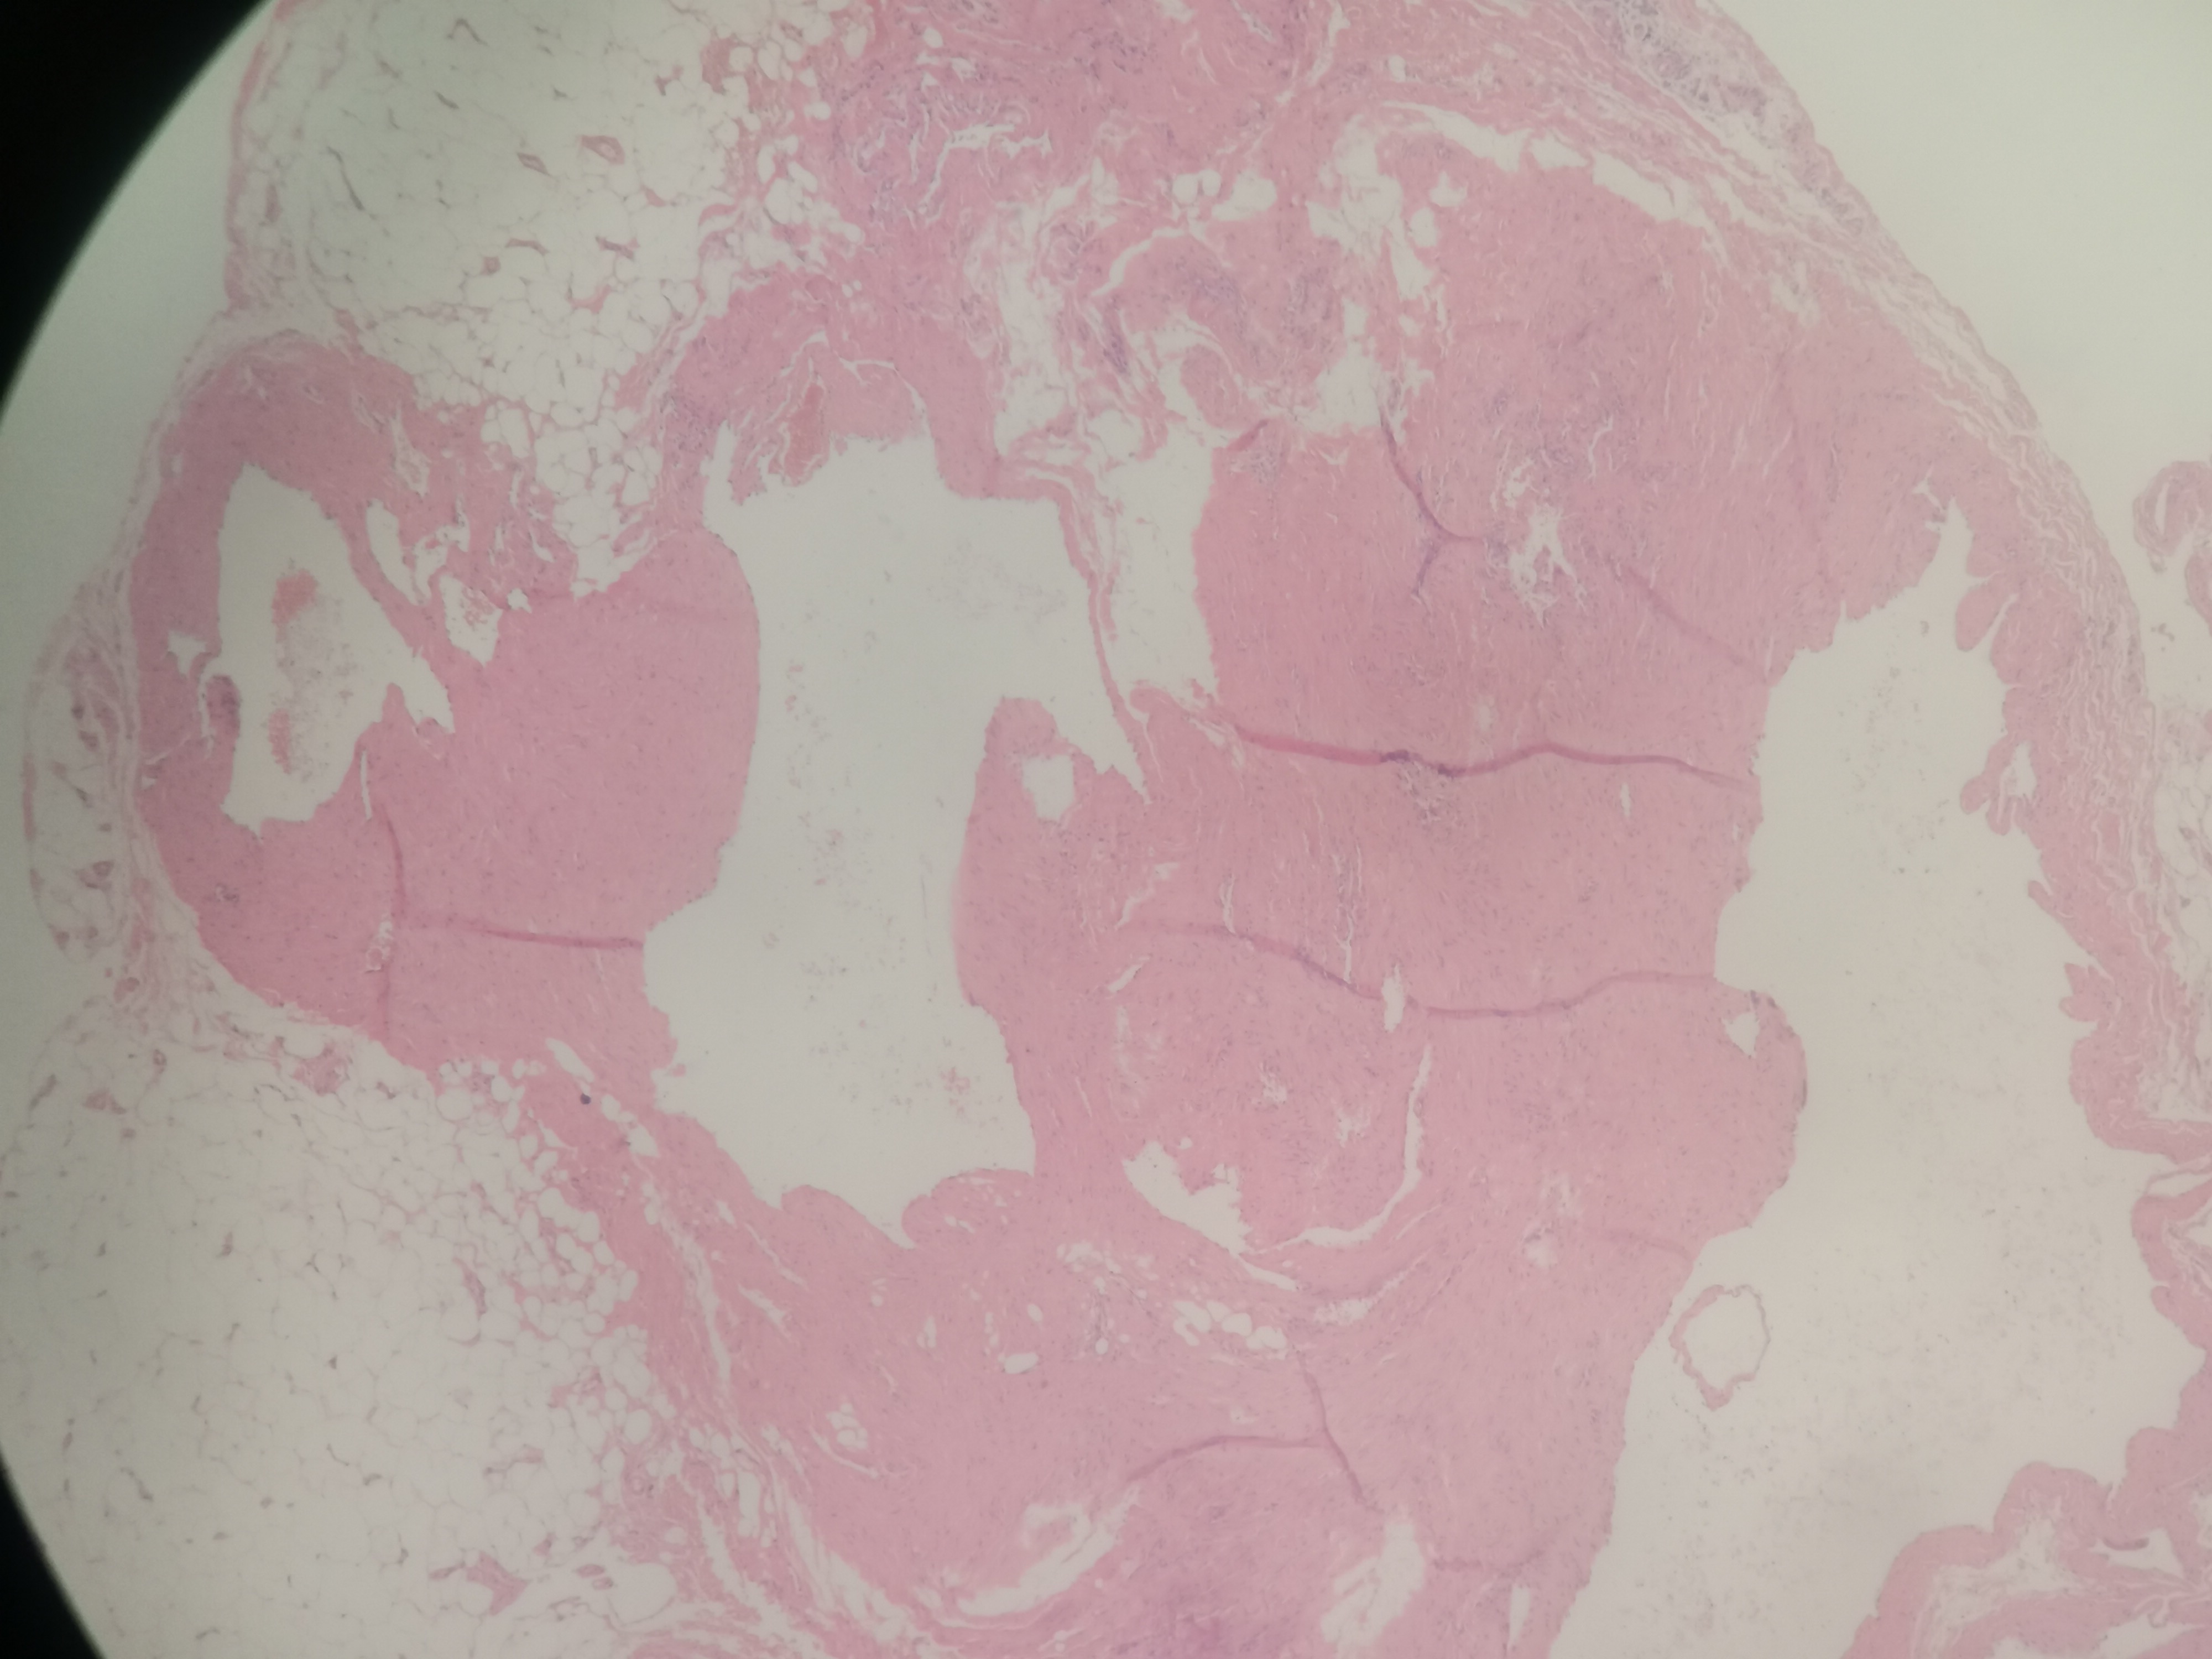

急!请老师帮忙看看,这个是血管瘤吗?

性别

女

年龄

47岁

临床诊断

右手拇指本部肿物

一般病史

发现肿物6个月,近一个月逐渐增大,疼痛,活动受限

标本名称

右手拇指本部肿物切除术

大体所见

送检组织2.0x(0.5~1.0)x(0.1~0.3)厘米,上见少量脂肪组织。

临床送检备注血管瘤 超声:右手虎口处皮下可见囊性回声,大下约:0.5*0.4cm,边界清晰,形态规整,CDFI:其内未见彩色血流信号。

动脉性血管瘤?

血管瘤。